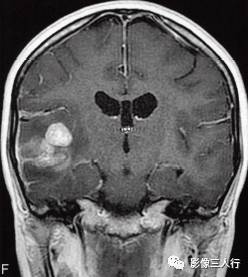

图1右颞叶横纹肌样脑膜瘤

A.T1WI横断面;B、C.T2WI横断面;D、E、F、G.增强横断面、矢状面、冠状面;H.HE×100

图1A:MRI T1WI示,右侧颞叶不规则形肿块,信号欠均匀,为稍低信号与小斑片状稍高信号混杂。其累及颞叶灰白质,界限欠清、边缘不整,大小约4.1cm×4.3cm×5.1cm。邻近脑沟脑裂变浅变平,周边脑实质受压。图1B、C:T2WI示,右颞不规则形肿块,信号欠均匀,为稍高信号与小斑片状略低信号混杂。灶周见带状高信号脑水肿。图1D~G:T1WI C示,右侧颞叶肿块呈不均匀的多个结节块状明显强化,邻近脑膜为线条状强化、增厚。